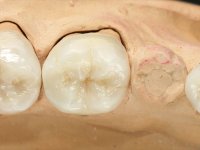

Realizado o diagnóstico e tomada a decisão quanto ao tratamento a executar, tornou-se importante definir qual a sequência de trabalho a adotar no sentido de conseguir a reabilitação da D.V.O. (V.D.O), de forma progressiva e equilibrada. Na primeira fase fez-se uma pré-impressão da arcada inferior com silicone tipo “putty” e em seguida realizou-se o preparo dentário de todo o sector posterior. O preparo para os overlays foi feito coronalmente à linha amelo cementaria no sentido de ser o mais conservador possível. A impressão foi feita com técnica de dupla mistura após afastamento gengival realizado com pasta de caulino. A provisória foi realizada com resina composta de polimerização dual. Em laboratório foram realizados os overlays após se ter aberto ligeiramente (1,5mm) a D.V.O. nos modelos montados em articulador semi-ajustável. Simultaneamente o sector antero-inferior foi encerado no sentido de acompanhar este aumento da D.V.O. Também foi confecionada uma chave de silicone translucido para posterior confeção dos provisórios antero-inferiores. Em boca foi primeiro realizada a provisionalização dos dentes anteriores utilizando resina composta previamente aquecida após preparação das superfícies dentárias para a adesão. Foi colocado o dique de borracha para promover o isolamento absoluto e posteriormente foram colados os overlays. Em laboratório foi realizada nova chave de silicone para confecionar os provisórios antero-superiores. Seguidamente em boca foram preparados os seis dentes antero-superiores após colocação do fio de afastamento gengival. Feita a preparação adequada das superfícies dentárias foi realizada a impressão com técnica de dupla mistura e a respetiva provisória. Em laboratório foram confecionadas 6 facetas feldespáticas num modelo de trabalho tipo “Geller”. A provisória foi removida e as facetas foram coladas em boca utilizando um isolamento relativo competente. Esta opção foi tomada em virtude de uma prévia experiencia negativa com a colocação do dique de borracha na mandibula. Após a colagem dos laminados antero-superiores foram dadas 12 semanas para avaliar a adaptação do paciente à nova situação e então iniciar a confeção das facetas antero-inferiores. Após colocação do fio de afastamento gengival. foram feitos os preparos dentários adequados e em seguida foi feita a impressão. Também foi feita a preparação do dente 3.4 que, entretanto, tinha sofrido uma fratura do overlay. As facetas e a restauração do 3.4 foram realizadas num modelo de trabalho tipo “Geller”. Após remoção da provisória, as facetas foram coladas em boca, utilizando um isolamento relativo pelas razões apontadas anteriormente. Após colocação do trabalho o paciente foi reabilitado por outros colegas com um implante na zona do 2.6 e substituição da coroa aparafusada sobre o implante colocado no local do 3.5. Posteriormente surgiram fraturas nos overlays dos dentes 4.7 e 3.7 que foram reabilitados com overlays em Zr.